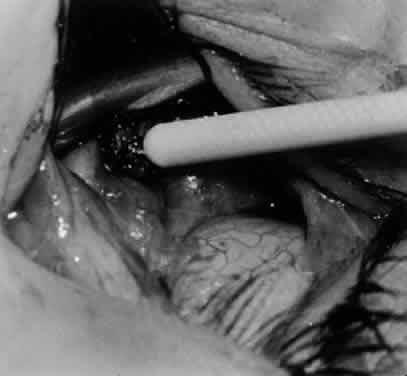

Fig. 3. The eye is retracted superonasally with the 4-0 silk traction suture. The suture is attached to the drapes with a hemostat. A Stevens hook is placed along the inferior border of the lateral rectus muscle and drawn temporally. A von Graefe hook is placed within the incision and drawn inferotemporally to expose the inferior oblique muscle.

Fig. 4. A stiff iris repositor can be placed against the sclera to depress the sclera and enhance the view of the inferior oblique muscle. The inferior temporal vortex vein adjacent to the Stevens hook is retracting tissue along the inferior border of the lateral rectus muscle. The second Stevens hook is pointing to the inferior oblique muscle.